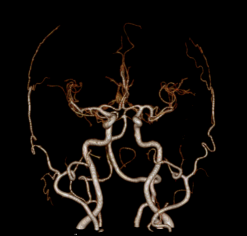

Chẩn đoán hình ảnh mô mềm tiên tiến cho vùng bụng.

Tăng cường độ tương phản I-ốt.

Hỗ trợ đánh giá an toàn cho bệnh nhân.

Đảm bảo hình ảnh chất lượng cao.